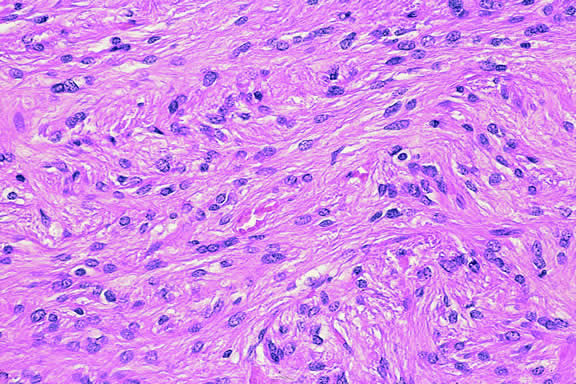

Histopathology

The cells comprising uveal melanoma constitute a biologic spectrum comprising bland spindle A melanoma cells at one end and wildly anaplastic epithelioid cells at the other. The term spindle cell is derived from the fusiform or spindled configuration of the cells' cytoplasmic outline. They are bipolar in shape, and many have long tapering processes that occasionally are highlighted when individual pigmented cells are seen in a largely amelanotic tumor. Spindle cells grow in a syncytial fashion forming interweaving fascicles of parallel oriented cells (Fig. 30). The cells can be pigmented or nonpigmented. Two types of spindle cells are recognized; spindle A and spindle B. These are distinguished by their nuclear characteristics. Spindle A nuclei are tapering ovals or cigar-shaped and have finely dispersed chromatin (Fig. 31). If a nucleolus is present, it usually is inconspicuous. Many spindle A cells have a longitudinally oriented chromatin stripe that actually is caused by a fold in the nuclear membrane. The nuclei of spindle B cells have distinct nucleoli and coarser chromatin and tend to be plumper and more oval in shape (Fig. 32).

Fig. 30. Amelanotic spindle cell melanoma. Tumor is composed of interweaving fascicles of spindle cells. Photomicrograph shows longitudinally and transversely sectioned fascicles. (Hematoxylin-eosin, × 100.)